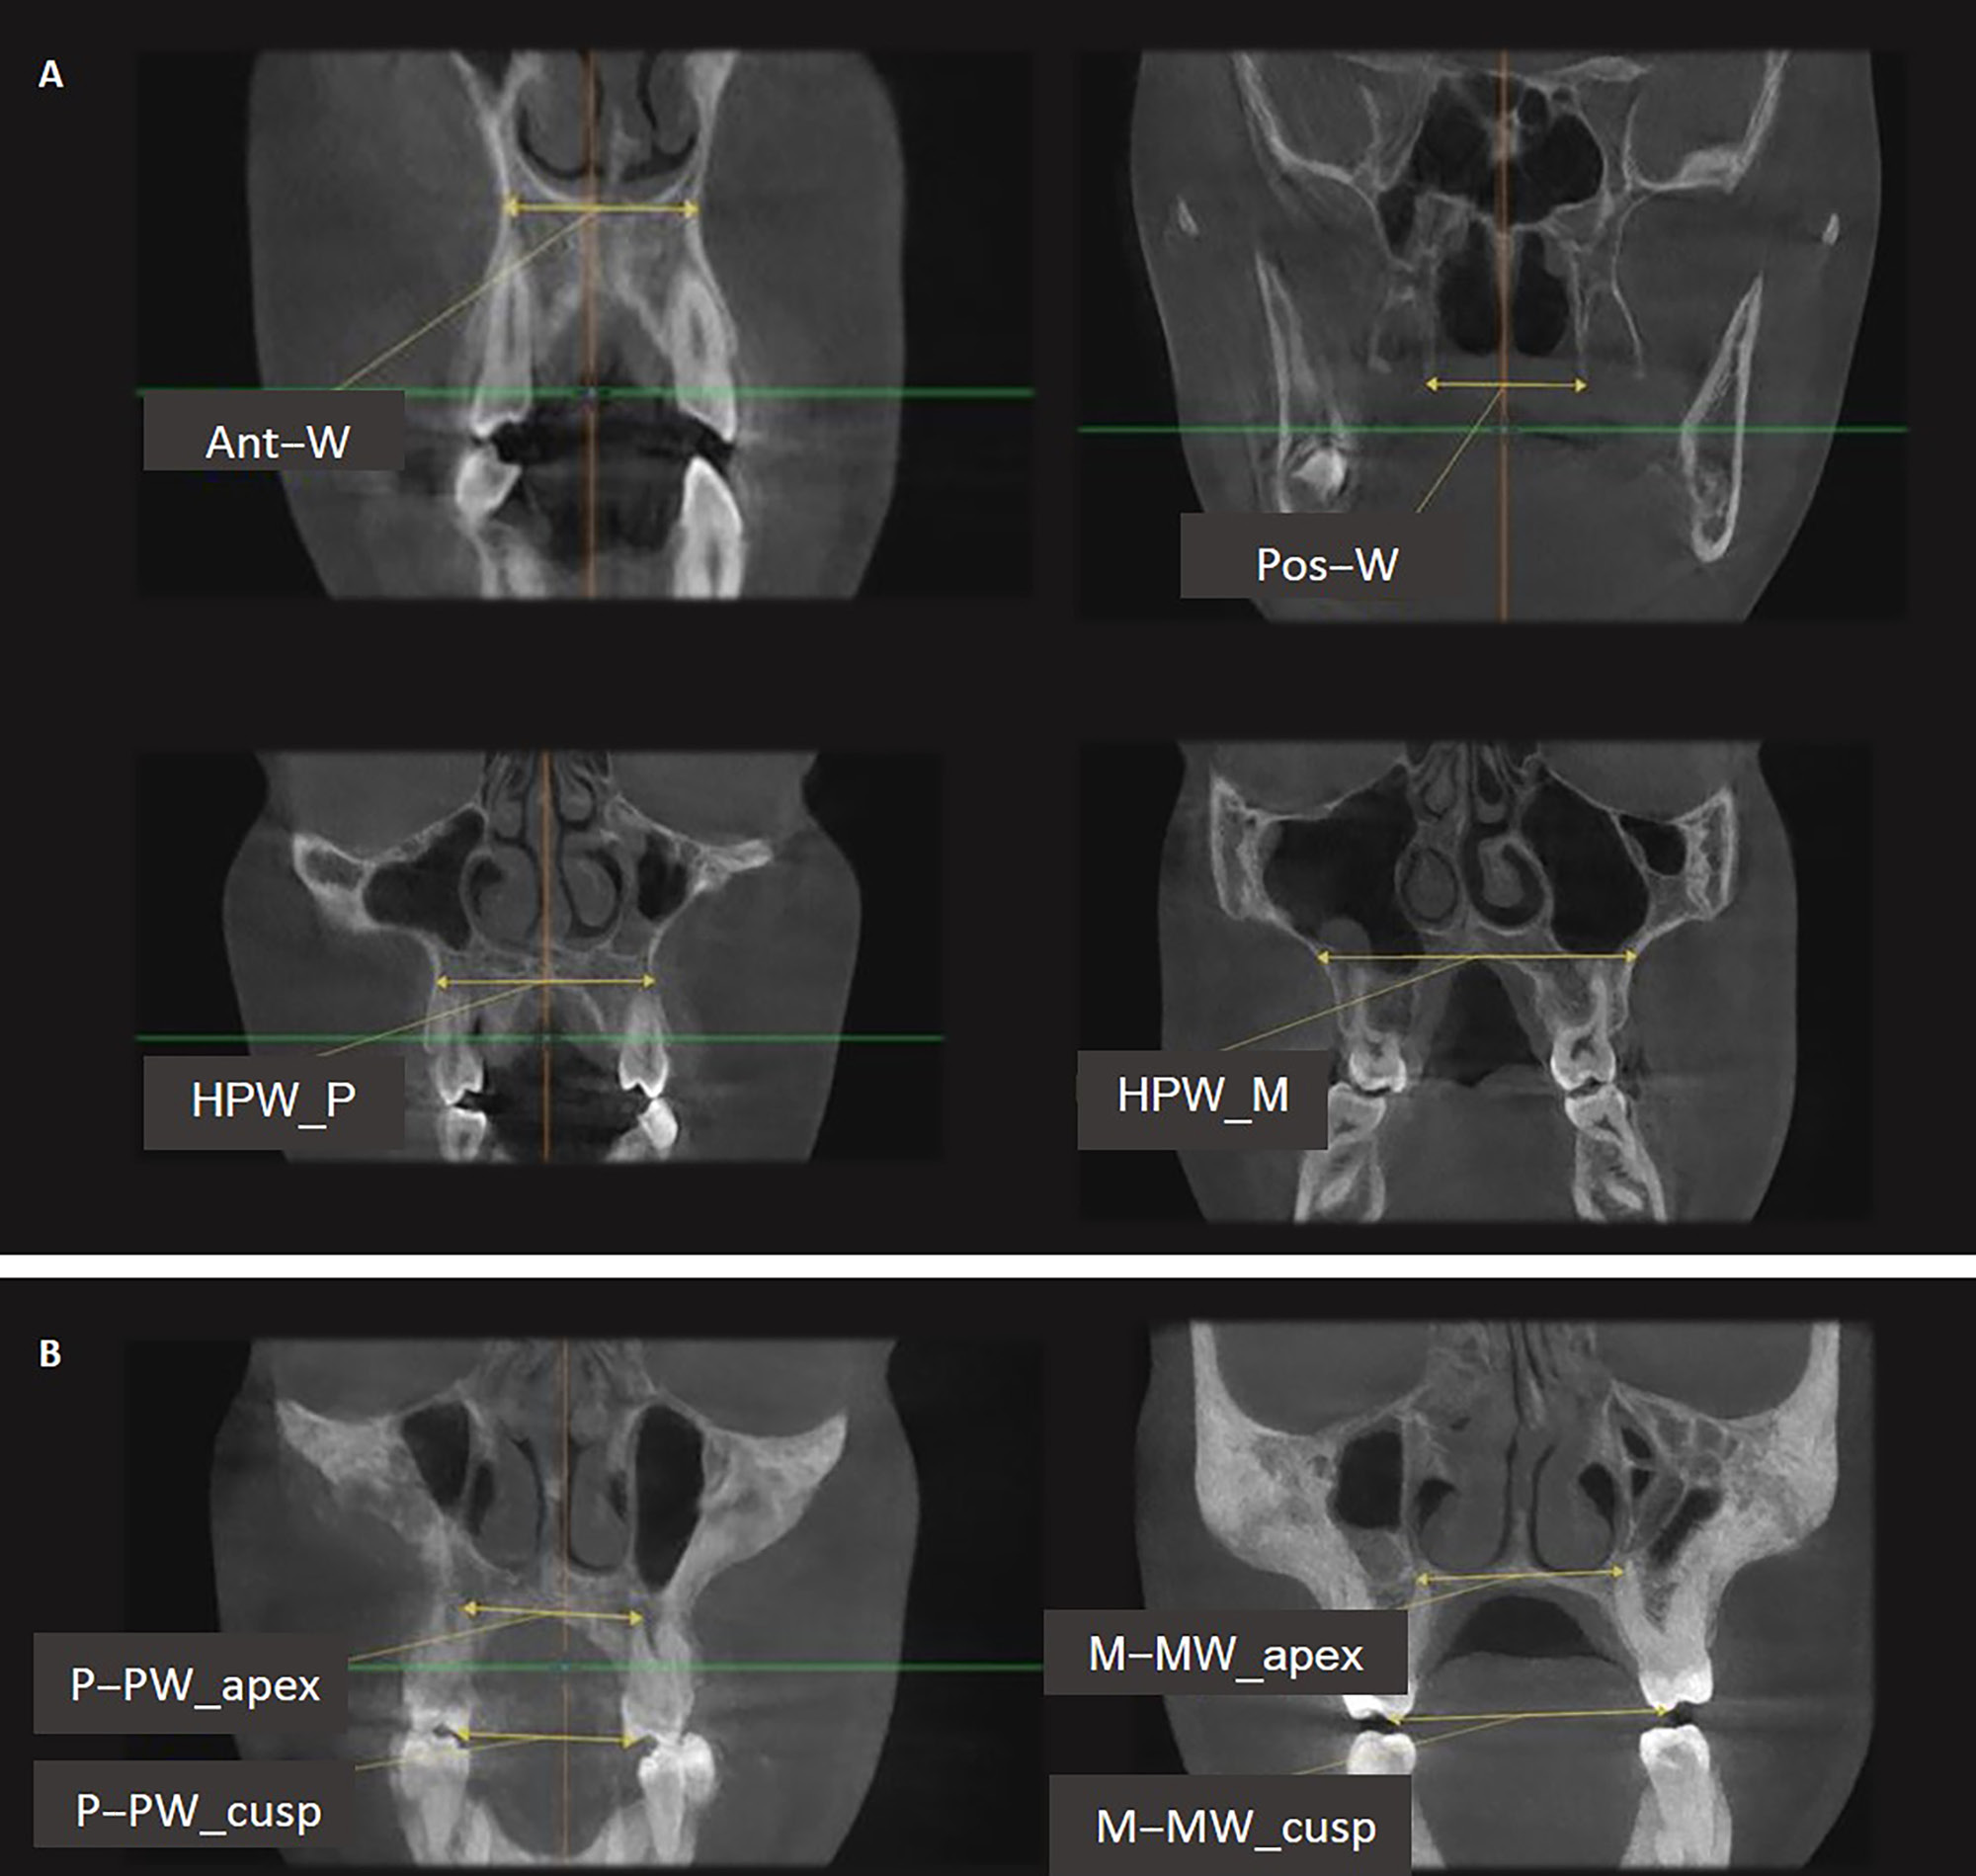

To ensure the appropriate position of the patient’s head, it was oriented in such a way that the Frankfurt plane was parallel to the horizon. The imaging system SCANORA® 3D (Soredex, Tuusula, Finland) was used (amperage: 12.5 mA; voltage: 90 kV; voxel size: 0.25 × 0.25 × 0.25 mm3; mean scanning time: 20 s). Two CBCT images were taken at the following time points: before expansion (T1); and 3 months after expansion and the removal of the appliance in the RME group, and 1 month after expansion and the removal of the appliance in the SME group (T2). Eight landmarks were identified on CBCT images: 4 skeletal landmarks (right/left pterygoideous point and right/left piriform point); and 4 dental landmarks (right/left root apex and right/left cusp tip) (Table 1).5 Four skeletal measurements were made: anterior palatal width; posterior palatal width; palatal width at premolars; and palatal width at molars (Table 1).5, 15 Six dentoalveolar measurements were made: inter-premolar width at the root apex; inter-premolar width at the cusp tip; inferred premolar tipping; molar width at the level of apices; molar width at the level of cusps; and inferred molar tipping (Table 1).5 Figure 3 and Figure 4 demonstrate the landmarks and measurements used. The definitions were derived from studies by Martina et al.5 and Lin et al.15 Both ‘inferred’ premolar and molar tipping measurements were given in millimeters (i.e., they were linear measurements), although they indirectly represented the amount of change in the buccolingual inclination of premolars and molars.5